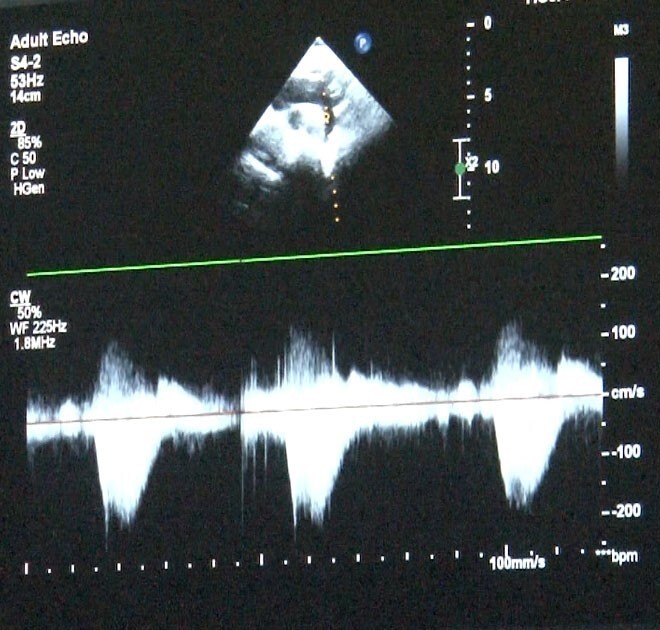

Türkiye'de doğan bebeklerin bir kısmı doğumsal kalp hastalıkları ile dünyaya gelmekte. Dr. Damla Gökçeer Akbulut, doğumsal kalp hastalığı teşhisi için zamanında tetkiklerin yapılmasının yaşamsal öneme sahip olduğunu belirtiyor. "Anne karnındaki fetal ekokardiyografi ile erken tespit mümkün," dedi.